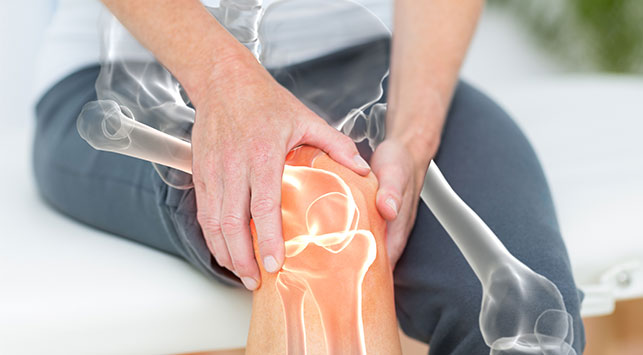

Radang Sendi Jari Tangan: Penyebab, Gejala, dan Pengobatannya

Radang sendi jari tangan merupakan salah satu keluhan yang cukup sering ditemui, terutama bagi Anda yang aktif menggunakan tangan untuk berbagai aktivitas sehari-hari. Mulai dari mengetik, memasak, hingga bermain alat musik, semua memerlukan kelincahan dan kekuatan jari yang sehat. Tapi, ketika radang sendi menyerang, aktivitas tersebut bisa menjadi terasa menyiksa. Artikel ini akan membantu Anda […]